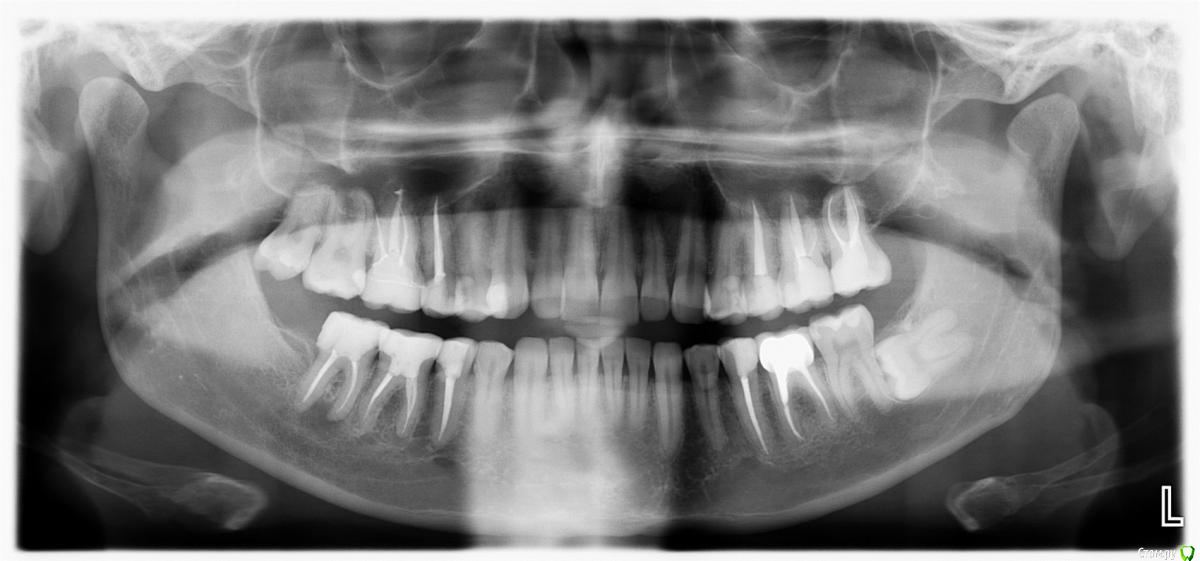

Ситуация такая, что начал лечение у ортодонта, но как оказалось, сильно исправлять прикус он не будет, только выравнивание зубного ряда. Расстояние выноса верхних зубов вперед в ширину четверки, но удалять четверки мне бы не хотелось. Так же, есть смещение в бок. Есть одна коронка и одна вкладка, много зубных каналов запломбировано. В целом, сильных проблем с прикусом я не ощущаю, но не будет ли потом проблем с челюстным суставом? Морально я готов к лечению, хотелось бы все сделать раз и навсегда, но с чего начать, какими способами нужно будет все исправлять? Придется ли делать операцию на челюсти или как то выносить нижнюю челюсть вперед другими способами? Нужно ли удалять восьмерки(осталась пара)?

И самое главное, необходимо найти грамотного специалиста и клинику, очень не хотелось бы иметь какие то проблемы со здоровьем после всех изменений, а так же бесконечного перелечивания, как у некоторых. Мне 31. Буду благодарен, если кто посоветует врача, желательно по собственному опыту или по хорошим отзывам в городе Москва, южная часть Подмосковья.